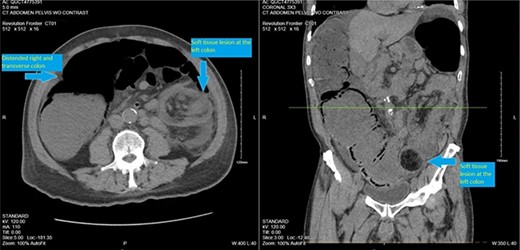

On presentation, the patient was afebrile with stable vital signs. Physical exam was significant for a markedly distended abdomen with generalized tenderness, worse on the left side with resonance on percussion. There were no abdominal hernias. The digital rectal examination revealed no lesions. The rectal tone was good and there was no stool in the vault. Laboratory evaluation showed hypokalemia (3 mmol/L) and mild anemia (hemoglobin 13.1 g/dl).A computed tomography (CT) scan of abdomen and pelvis was performed and showed colonic intussusception in the descending colon with a possible lipoma/ fat containing lesion associated with the wall of the distal left colon and proximal sigmoid colon measuring 4.2 cm × 4.3 cm (Figs 1–3). There was marked distended right colon and transverse colon but no sign of bowel perforation or free air seen. There is mucosal thickening of the left colon with pericolic stranding. Developing ischemia of the left colon could not be ruled out. With the findings on imaging, it was determined that the patient would undergo an exploratory laparotomy with left hemicolectomy to remove the intussuscepted bowel.

CT scan pelvis (axial and coronal cuts) showing a soft tissue lesion in the left colon, with surrounding fat stranding and distended right and transverse colon.